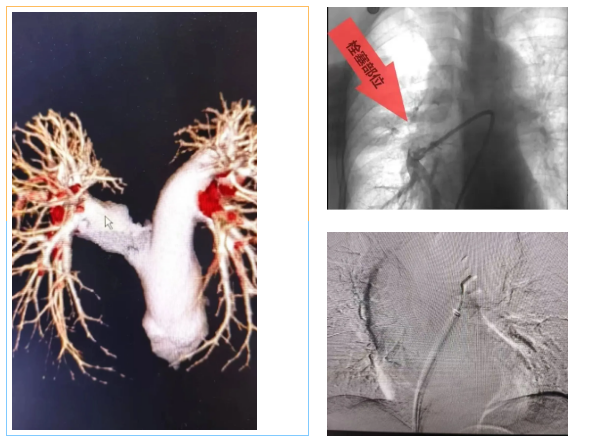

近日,洛阳白马医院内二科与介入科团队成功为一名74岁的高危肺栓塞患者实施了联合介入治疗。该患者高龄、血栓负荷重,且血小板水平较低,病情复杂、风险较高。面对这一挑战,内二科与介入科医生共同制定了适合患者个体条件的介入方案,由介入科独建库主任在DSA(数字减影血管造影)引导下,依次完成肺动脉造影、血栓抽吸、静脉滤器植入,并配合抗凝治疗。整个手术采用微创方式,术后患者状态平稳,症状明显改善,目前已进入后续康复阶段。

值得一提的是,此次治疗是内二科成功开展的首例肺动脉介入治疗(肺动脉造影+血栓抽吸),标志着科室在肺血管疾病微创诊疗方面迈出了重要一步。

• 介入取栓:微创,用导管直接把血栓抽出来,见效快——本案例采用的就是这种方法。

• 静脉滤器植入:在血管里放一个“小网兜”,拦住脱落的血栓,防止再次发生肺栓塞。